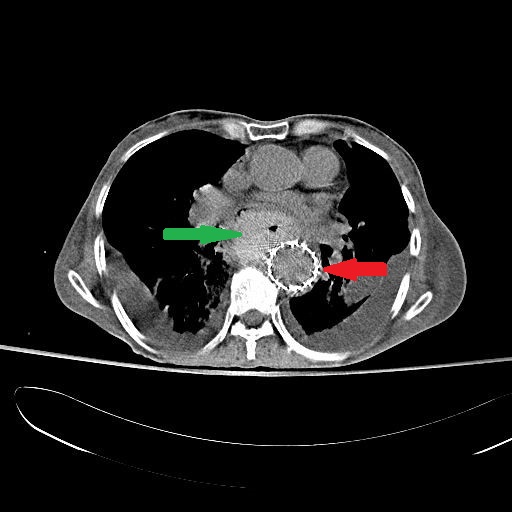

CT θώρακος 6η μετεγχειρητική ημέρα: αυξημένη συσσώρευση αέρα στο μεσοθωρακικό αιμάτωμα (κόκκινα βέλη) (Ευγενική παραχώρηση Dr. V. Penopoulos)

CT θώρακος 3η μετεγχειρητική ημέρα: Αορτικό stent σε θέση (κόκκινο βέλος). Ελάχιστος αέρας στο μεσοθωρακικό αιμάτωμα (πράσινο βέλος) (Ευγενική παραχώρηση Dr. V. Penopoulos)